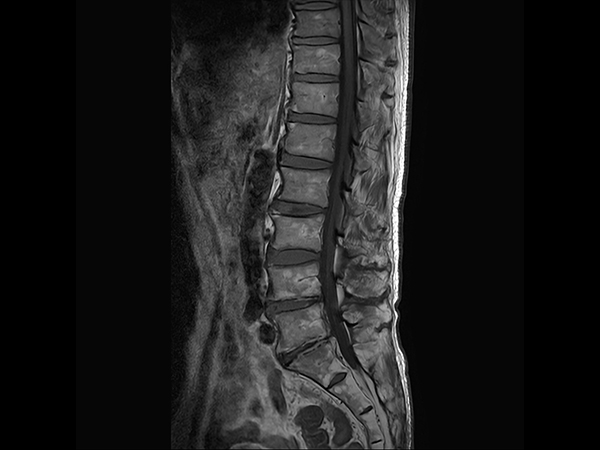

Lumbar Spine fracture with SmartSpeed Precise

Sagittal T1w TSE